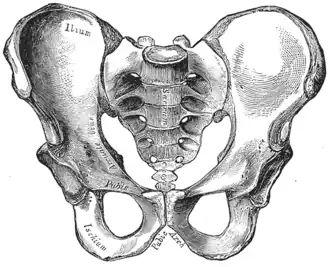

| Comparison between an android (left) and a gynecoid pelvis (right). | |

Traditional obstetrical services relied heavily on pelvimetry in the conduct of delivery in order to decide if natural or operative vaginal delivery was possible or if and when to use a cesarean section.[9] Women whose pelvises were deemed too small received caesarean sections instead of birthing naturally.

Traditional obstetrics have characterized four types of pelvises:

- Gynecoid: Ideal shape, with round to slightly oval (obstetrical inlet slightly less transverse) inlet.

- Android: triangular inlet, and prominent ischial spines, more angulated pubic arch.

- Anthropoid: the widest transverse diameter is less than the anteroposterior (obstetrical) diameter.

- Platypelloid: Flat inlet with shortened obstetrical diameter.